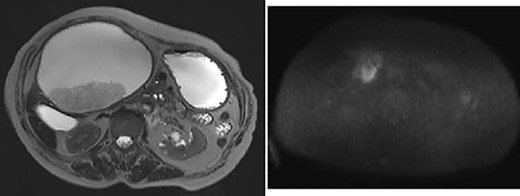

The hepatic cyst compressed the stomach, duodenum, pancreas and gallbladder, and the descending part of the duodenum was difficult to identify because of severe thinning caused by the compression. On magnetic resonance imaging, the giant cyst showed low signal intensity on T1-weighted and high signal intensity on T2-weighted images, and there was a solid component with a high signal on diffusion-weighted images on the dorsal side of the cyst (Fig. 2).

Giant cyst showed high signal intensity on T2-weighted images and fuller component in dorsal side showed high signal on diffusion-weighted images.